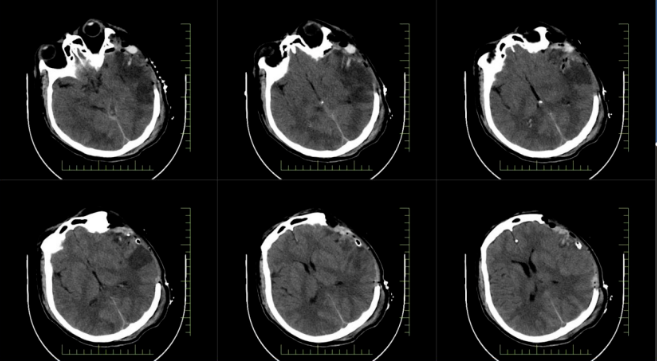

術(shù)中探查患者顱內(nèi)出血量極大,腦組織水腫嚴(yán)重,受壓明顯。在神經(jīng)外科張友軍主任的帶領(lǐng)下,手術(shù)團(tuán)隊(duì)?wèi){借精湛的醫(yī)術(shù)和豐富的經(jīng)驗(yàn),爭(zhēng)分奪秒地進(jìn)行止血操作,降低顱內(nèi)壓。經(jīng)過(guò)長(zhǎng)達(dá) 4 小時(shí)的艱苦奮戰(zhàn),手術(shù)成功完成,患者隨即轉(zhuǎn)入重癥醫(yī)學(xué)科接受進(jìn)一步監(jiān)護(hù)。

*患者顱內(nèi)術(shù)后影像圖

在 ICU 團(tuán)隊(duì) 24 小時(shí)不間斷的悉心守護(hù)下,郭先生闖過(guò)了腦水腫、感染等一道道難關(guān)。一周后,他的意識(shí)逐漸清醒,順利轉(zhuǎn)入普通病房。目前,在家人的攙扶下,郭先生已能適當(dāng)下床活動(dòng),語(yǔ)言和肢體功能恢復(fù)狀況良好。